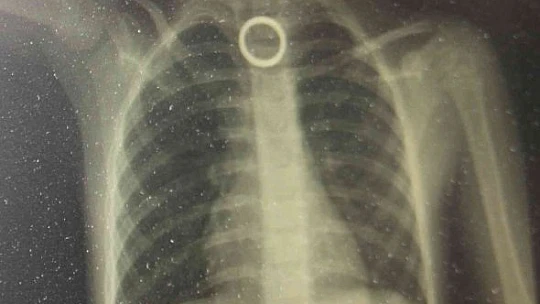

Elazığ'da 3 yaşındaki çocuğun yutması sonucu yemek borusuna sıkışan yüzük, yapılan cerrahi operasyonla çıkartıldı.

Elazığ’da evde oyun oynayan 3 yaşındaki çocuk, yakınında bulunan yüzüğü yuttu. Durumu fark eden ebeveynler çocuğu hemen Fırat Üniversitesi Hastanesine getirerek Çocuk Gastroenteroloji Ana Bilim Dalı Başkanı Prof. Dr. Yaşar Doğan’a gösterdi. Burada yapılan tetkiklerde yutulan yüzüğün yemek borusu birinci darlık kısmında takılı kaldığı görüldü. Hemen Çocuk Endoskopi Ünitesine alınan 3 yaşındaki çocuğun boğazındaki yüzük yapılan endoskopik yöntemle çıkartıldı. Sağlık durumu iyi olan çocuk taburcu edilirken, uyarılarda bulunan Çocuk Gastroenteroloji Ana Bilim Dalı Başkanı Yaşar Doğan, bu tür vakaların meydana gelmemesi için ailelerin, çocukların etrafından bulunan yabancı cisimleri uzaklaştırmaları gerektiğini belirtti.

Hastanın 3 yaşında olduğunu belirten Çocuk Gastroenteroloji Ana Bilim Dalı Başkanı Prof. Dr. Yaşar Doğan, "Bu hastamız akşam saatlerinde boğazına yabancı cisim yutma yakınmasıyla ailesi tarafından hastanemize getirildi. Yaptığımız incelemeler neticesinde özellikle yemek borusunun birinci darlık kısmında yüzüğü benzer bir yabancı cisim gördük. İlk geldiğinde hasta yeni beslendiğinden dolayı endoskopi için açlık süresi bekletildi. Ondan sonra gerekli olan endoskopi işlem yapılarak oradaki yabancı cisim çıkartıldı. Çıkarma işlemi başarılı bir şekilde yapıldıktan sonra aile 2 saatlik gözlemden sonra evine gönderildi. Şu anda herhangi bir sıkıntısı yok. Bu gibi vakalar bize çok fazla gelmektedir. Özellikle mevsimler değişkenlik dönemlerinde evlerde temizliğin yapıldığı dönemlerde ailenin çocuğu rahatlıkla gözlemleyemediği dönemlerde çocuklar etrafında buldukları her yabancı cismi ağızlarına götürme eylemindeler. Özellikle yabancı cismin nefes borusu veya akciğer kaçması ölümcül nedenlere yol açabilir ama yemek borusu veya sindirim sistemine kaçmış olan yabancı cisimler erken getirildiği zaman endoskopik yöntemlerle çıkarabilmekteyiz. Bu tür vakaların meydana gelmemesi için ailelerin tam bilinç seviyesi yerine gelmemiş çocukların etrafında yutabilecekleri bütün yabancı cisimleri uzaklaştırması gerekir. Yoksa çok kötü sonuçlarla karşılaşabiliriz” dedi.